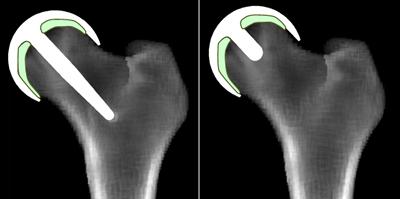

Virtual x-Rays showing Predictions of Bone Remodelling and Healing around Hip Resurfacing Implant Concepts

Virtual x-Rays

These tools will aid the development of new implant concepts, and predict their performance to assess whether a concept is safe to begin clinical evaluation. Details of direct research impact from this project can be found here .